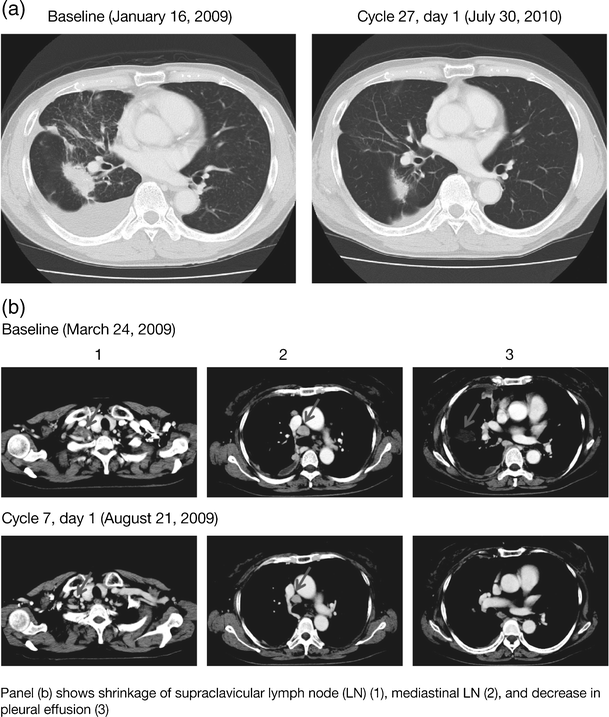

Of 13 evaluable patients, one experienced a PR as a BOR per RECIST. The PR (treatment duration 767 days) was observed in a patient with NSCLC (adenocarcinoma, male, 70 years) in the 15 mg cohort (Table 4, Fig. 2a). No patient had a CR. SD (≥6 weeks) was observed in nine patients: three in the 30 mg QD cohort and six in the 45 mg QD cohort (NSCLC, n = 6; colorectal carcinoma, n = 1; breast cancer, n = 1; squamous cell neoplasm, n = 1). One patient with SD (28.7% reduction) was a 66-year-old never-smoking female who, following a PR on gefitinib, was found via analysis of pleural effusion to have adenocarcinoma of lung characterized by both L858R and secondary_T790M_ mutations; she started dacomitinib 30 mg 79 days after discontinuation of gefitinib and continued for 134 days (8 cycles) before progression (Fig. 2b). Progressive disease (PD) was observed in three patients (15 mg QD cohort, n = 2; 45 mg QD cohort, n = 1). Four of eight patients with NSCLC had tumor size reductions (Table 4).

Fig. 2

Pre- and post-treatment computed tomography: a 70-year-old patient with NSCLC (Table 4, patient No. 1) (a) receiving dacomitinib at 15 mg QD; and a 66-year-old patient with NSCLC (Table 4, patient No. 4) (b) receiving dacomitinib at 30 mg QD

While these data are limited by the small sample size, antitumor activity was suggested in these Japanese patients. One of eight patients with NSCLC achieved a PR and six patients experienced SD (≥6 weeks) as best response. One patient with NSCLC (adenocarcinoma, ex-smoker, male, 70 years [Table 4]) who had an exon 19 deletion and who was EGFR tyrosine kinase inhibitor treatment-naïve experienced a PR (57.7% reduction) as best response following treatment with dacomitinib 15 mg QD, and had an extended treatment duration of 25 months (767 days) (Fig. 2a). One further patient with NSCLC, with an exon 21 mutation (L858R) and T790M secondary mutation, had sustained SD (179 days, 28.7% reduction) (Fig. 2b). Approximately 50% of the acquired resistance to EGFR tyrosine kinase inhibitors such as gefitinib and erlotinib has been considered to be due to the presence of the T790M EGFR mutation [23] and, as treatment with pan-HER inhibitors (such as dacomitinib, afatinib, and neratinib) has not previously been reported to be beneficial in patients with known T790M resistance, the degree of benefit observed in this patient is noteworthy.